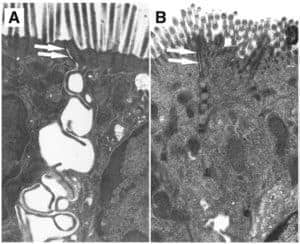

Colic Researchers: Tight Junctions Crucial in Gut Function

A research team is examining how infectious disease and inflammation impact cells in the horse’s gut.